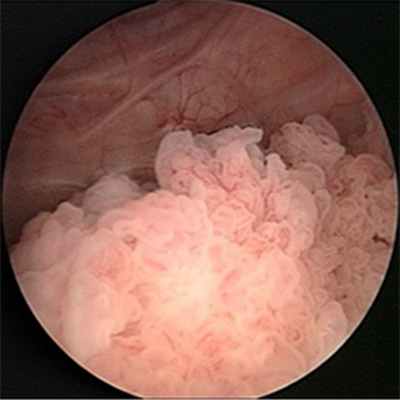

Наиболее частой формой рака мочевого пузыря является переходно-клеточный рак (95%) (развивающийся из переходного эпителия мочевых путей), реже встречаются плоскоклеточный рак и аденокарцинома (опухоль, происходящая и построенная из железистого эпителия). Опухоль в мочевом пузыре может быть в виде папиллярных разрастаний («цветная капуста») или солидной, изъязвлённой, инвазирующей опухоли. По течению процесса и применяемому лечению различают рак мочевого пузыря in situ, мышечнонеинвазивный рак (Т1-2) и инвазирувный рак с прорастанием только в мышечный слой и окружающие ткани (ТЗ-4).

Главным методом диагностики рака мочевого пузыря, которое проводится обычно на заключительном этапе является цистоскопия с биопсией и гистологическимисследованием.

Цистоскопия – основной метод диагностики рака мочевого пузыря. Это процедура, в ходе которой уролог с помощью специального оптического прибора производит осмотр внутренней поверхности мочевого пузыря.

Цистоскопия позволяет врачу увидеть опухоль, а также взять кусочек опухоли для гистологического исследования. Это исследование может быть не очень приятным, так как необходимо ввести цистоскоп в мочевой пузырь через мочеиспускательный канал.

- Эндоскопия позволяет визуально обнаружить внешний вид неоплазии, её размер и локацию. К тому же это обследование даёт возможность взять биопсию и осуществить морфологическое подтверждение рака мочевого пузыря.